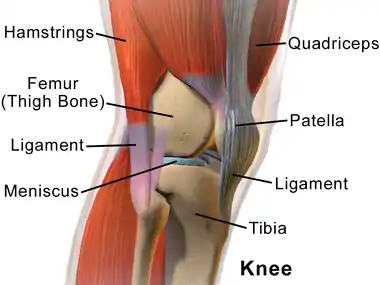

Knee from the side, with lateral meniscus simply labeled as "meniscus". | |

| |

The lateral meniscus (external semilunar fibrocartilage) is a fibrocartilaginous band that spans the lateral side of the interior of the knee joint. It is one of two menisci of the knee, the other being the medial meniscus. It is nearly circular and covers a larger portion of the articular surface than the medial. It can occasionally be injured or torn by twisting the knee or applying direct force, as seen in contact sports.